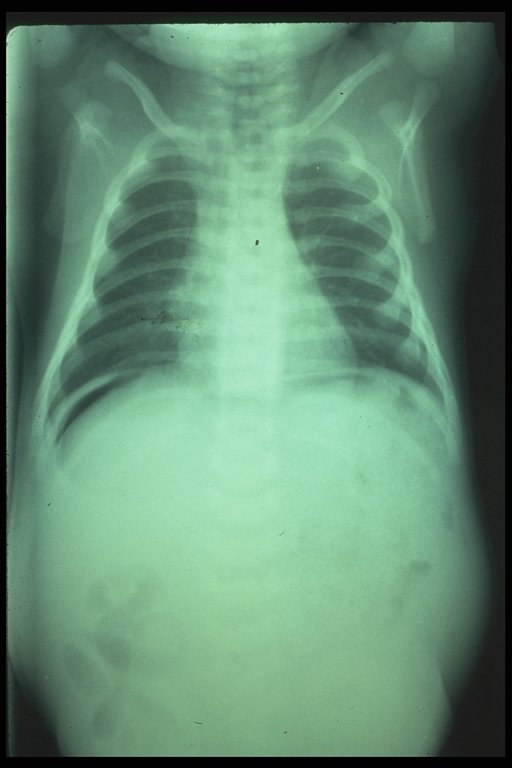

Free air under the dome of right diaphragm indicates that there is bowel perforation

Large gas shadow at the central abdomen in the supine film and the well outlined falciform ligament (white line) indicates bowel perforation